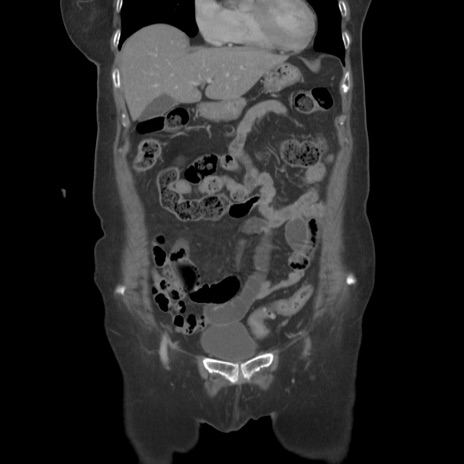

症例19(冠状断像)

横断像

【症例】80歳代女性

【主訴】下腹部痛

【現病歴】約8時間前より下腹部痛の出現あり、救急外来受診。

【既往歴】両側付属器切除

【身体所見】意識清明、下腹部正中に手術痕あり、その部位に一致して圧痛と反跳痛あり。腸蠕動音は亢進。

【データ】WBC 9300、CRP 0.15